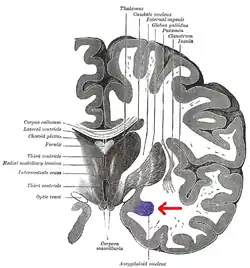

Amígdala en azul. Corte coronal del encéfalo.

Además, resultados recientes sugieren que las diferencias sexuales en la amígdala podrían correlacionarse con diferencias hemisféricas de la amígdala. Cahill y otros[6]​ sugieren una teoría «derecha-varón, izquierda-mujer» de la actividad de la amígdala. Así, las conexiones con la amígdala derecha facilitan un mejor seguimiento o vigilancia de estímulos externos, y las conexiones con la amígdala izquierda facilitan un mejor seguimiento o vigilancia de estímulos internos.